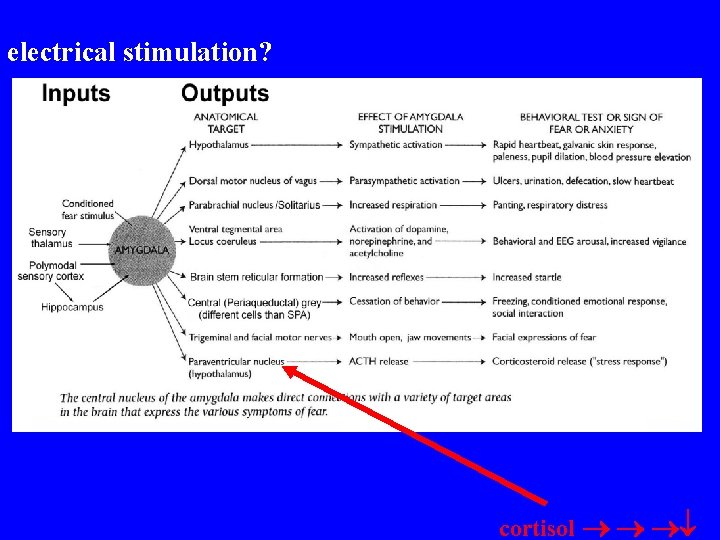

electrical stimulation? cortisol